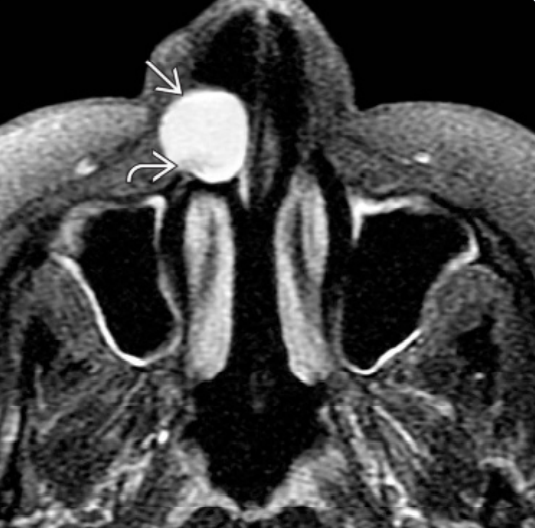

3.2. Ρινοχειλική ή Ρινοφατνιακή Κύστη

Οι ρινοχειλικές κύστεις εντοπίζονται στα μαλακά μόρια του άνω χείλους. Είναι σπάνιες βλάβες με την κορύφωση της επίπτωσής της να παρατηρείται στην 4η και 5η δεκαετία της ζωής.

Το κύριο κλινικό σημείο είναι η διόγκωση των μαλακών μορίων, που παρουσιάζεται στην περιοχή των κυνοδόντων ή της ουλοχειλικής αύλακας. Ακτινογραφικά εμφανίζεται διαύγαση στην περιοχή του τομικού πόρου.

Η κύστη αντιμετωπίζεται με εκπυρήνιση και αναμένονται λίγες υποτροπές.